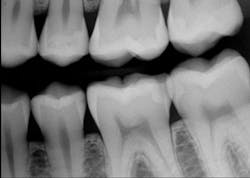

Figure 1: Apparently small caries on distal of mandibular second premolar

Figure 3: Tooth preparation initially cut (left) and cut deeper (right) showing inadequacy of current generation of digital bitewings to show full extent of caries as related to radiograph